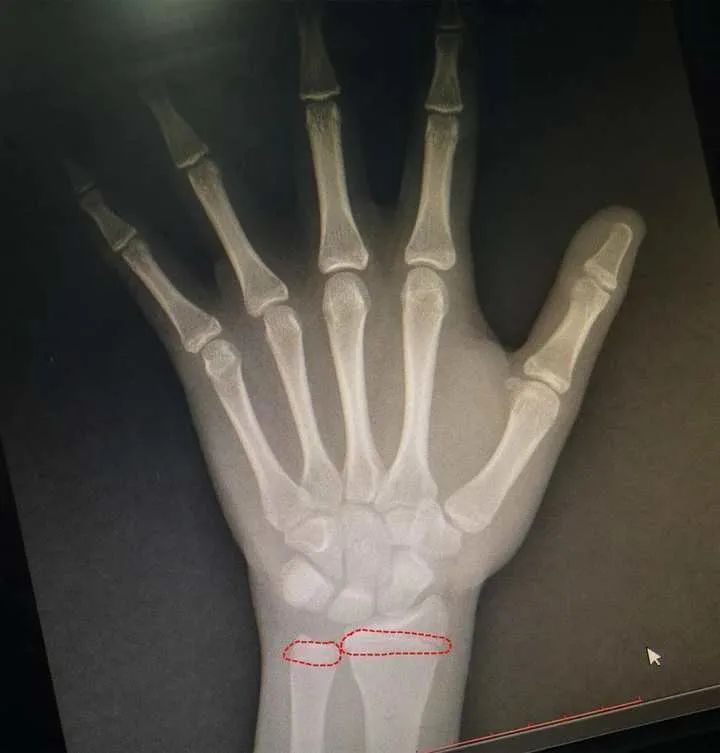

13岁小振的骨龄片“也就是说,已经几乎没有长高的空间了!”树兰(杭州)医院儿科主任覃珍主任医师介绍,原本按照孩子父母的身高,小振的身高能长到172cm,但是肥胖导致他提早发育,提前透支了他的生长空间。妈妈在一旁后悔,“他自己也知道太胖了,最近一年都在减肥,但还是来不及了。”妈妈赶紧拉来小振的弟弟,“医生,帮我们给弟弟也看下,千万不能让他和哥哥一样。”弟弟(小林)今年6岁,也是个小胖墩,个头也不小,“身高128cm,体重70斤,血糖和尿酸指标已经有异常了。一定要提前干预,提早预防了!”相比较这对亲兄弟,10岁的小志(化名)的情况更棘手。“小朋友已经有一百斤,一年前曾在其他医院减肥失败,今年来医院检查,患有高脂血症,空腹血糖和糖耐量试验受损,如果再不加以控制,病情下一步进展就是糖尿病。”覃珍主任医师通过详细问诊,发现小志有家族遗传史,父亲30多岁时患二型糖尿病,不良饮食结构+遗传基因,导致了十岁孩子患上“糖尿病前期”。医生除了药物调整胰岛素分泌外,还叮嘱小志一定要调整饮食,迈开腿多运动。在覃珍主任的指导下,小志妈妈调整了每日菜单。每天早上摄入优质蛋白质,搭配粗粮谷物以及低糖果蔬,晚餐也控制总量,进食时间和顺序也有严格要求。